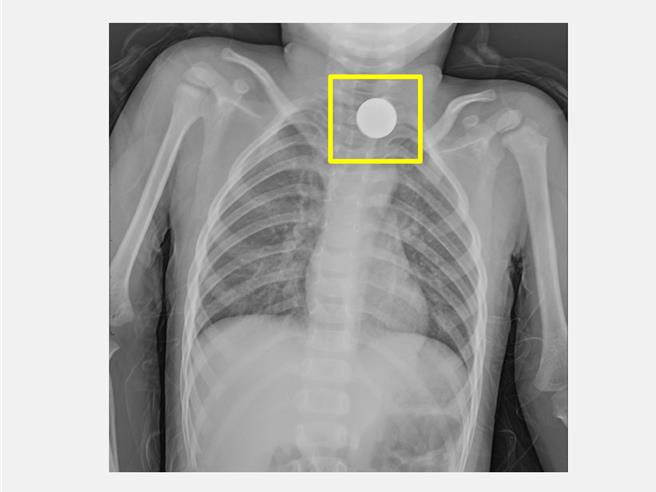

台中3歲男童日前疑似吞入異物出現喉嚨痛和吞嚥不適,被送到仁愛長庚合作聯盟醫院急診室,照X光查出其食道處有一環狀扁平異物,緊急安排全身麻醉腸胃鏡異物夾取術取出1元硬幣。(仁愛長庚合作聯盟醫院提供/潘虹恩台中傳真)

台中3歲男童日前疑似吞入異物被送到仁愛長庚合作聯盟醫院急診室,醫師檢查發現男童有喉嚨痛和吞嚥不適,並無呼吸窘迫、皮下氣腫與喘鳴呼吸音,照X光查出其食道處有一環狀扁平異物,緊急安排全身麻醉腸胃鏡異物夾取術,耗時2小時終於取出1元硬幣,讓家長放下心中的大石。